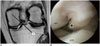

Fig. 2

44-year-old woman with partial tear of anterior cruciate ligament.

Proton density weighted (repetition time, 2200 msec; echo time, 30 msec) coronal MR image (A) of left knee shows focal outward bulging contour at medial margin of PCL, confined to medial side of line between inferomedial corner of medial femoral condyle and medial tibial spine (arrow). This case was classified as positive for interposition of PCL into medial compartment of knee joint. Arthroscopic image of medial compartment obtained with knee flexion position (B) shows same focal outward bulging contour of PCL (asterisk) between medial femoral condyle (MFC) and medial tibial plateau (MTP). PCL = posterior cruciate ligament